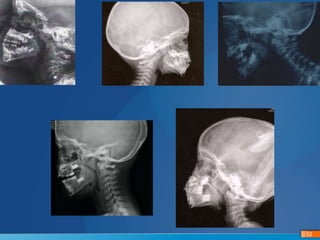

 Rétrognatisme ou autre malformation faciale

• Attention au rétrognatisme source de persistance des apnées